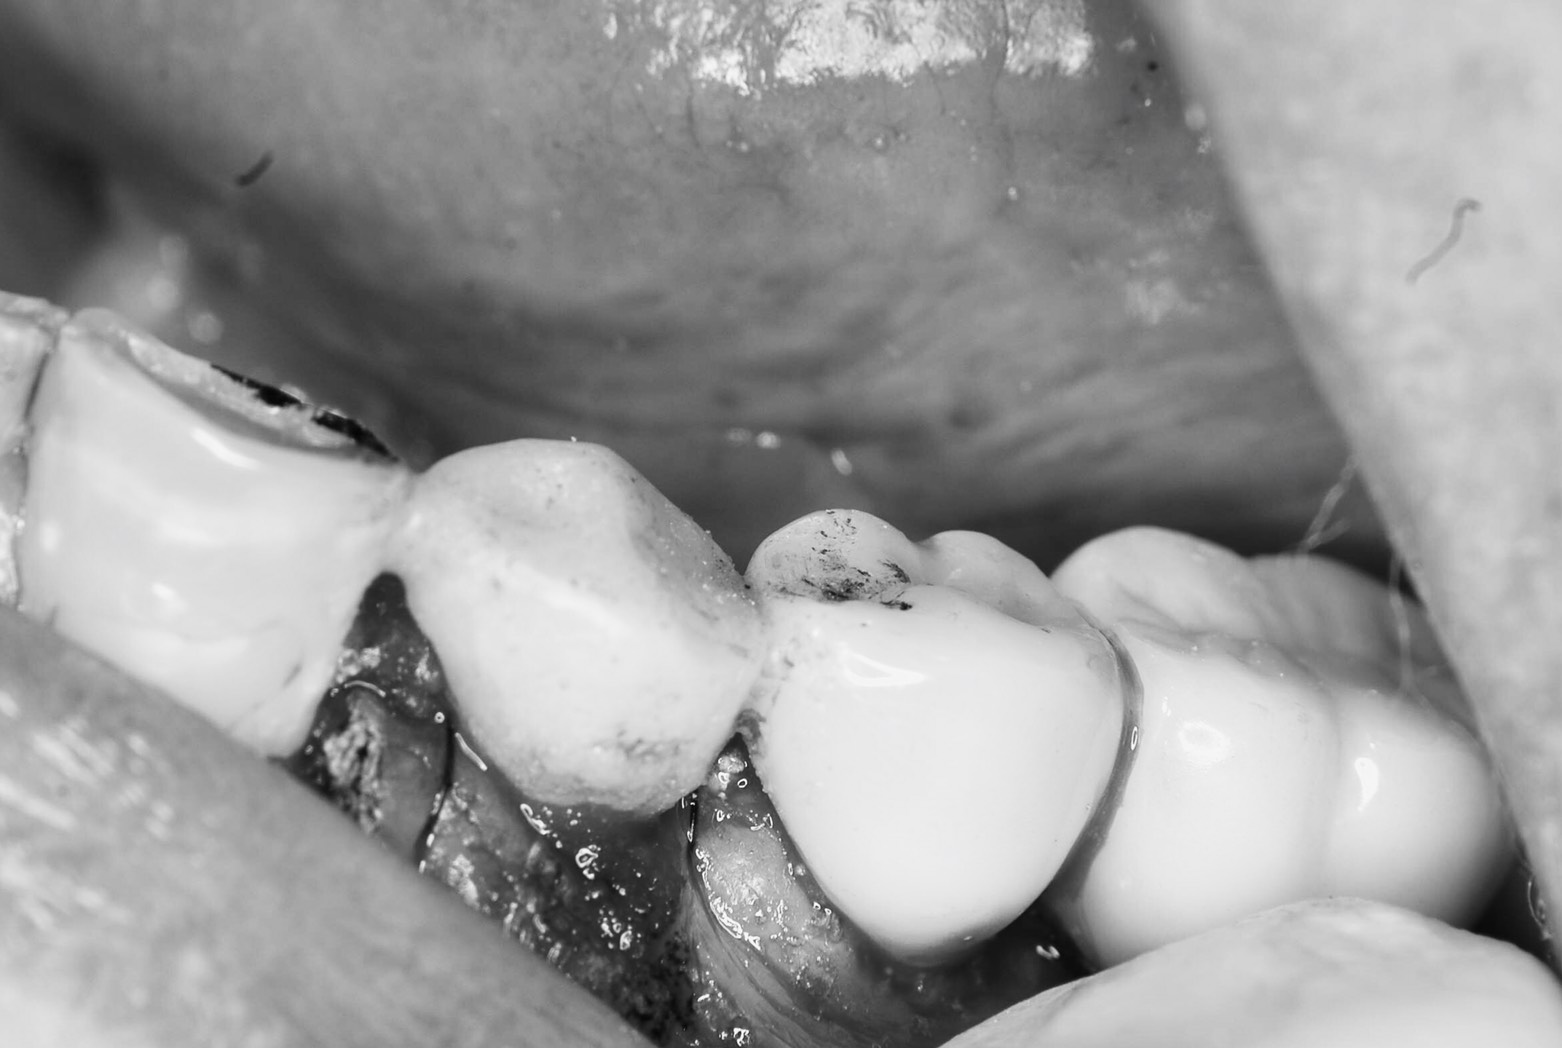

左下4番の抜歯と同時にインプラントの埋入オペをし、即時に仮歯を装着し噛めるようにする難易度の高いオペです。患者さんは2週間前にも右下に同様のオペをされた方です。

骨質を見極めたドリリングテクニックはいつもの様にスムーズに行われ骨との合着値も良い結果が出ています。

患者さんのご希望である『早く食生活の向上を得たい』に添える結果に。しっかり良く噛んで健康な体作りは患者さん自身の抵抗力を上げる大切な要因です。須田医師が日々目指す『患者さんの為にキチンと努力する』がまっとうされた本日のオペでした。